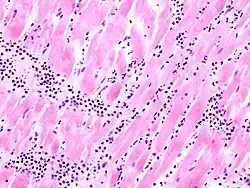

Acute myocardial infarction

Der Myokardinfarkt muss mind. 6 - 12 Stunden überlebt werden, bevor er morphologisch sichtbar wird!

Mikro: Koagulationsnekrose, Einblutungen. Die Myozyten zeigen eine verstärkte Eosinophilie und Kontraktionsbanden quer durch die Herzmuskelfasern. Typische Zellparameter wie Querstreifung, Zellkerne und Zellgrenzen gehen verloren. Das Infarktareal wird von einer Hyperämischen/hämorrhagischen Randzone begrenzt. Im Verlauf zunehmende leukozytäre Demarkation und Phagozytose des nekrotischen Gewebes, sowie Einwanderung von Fibroblasten mit Ausbildung eines narbigen Ersatzgewebes.

Makro: Lehmfarbene Abblassung mit hyperämischem/hämorrhagischem Randsaum.

Kompl.: Herzwandruptur mit Perikardtamponade (i.d.R. zwischen dem 3. und 10. Tag), Herzwandaneurysma, Papillarmuskelnekrose mit Sehnenfadenabriß, Herzrhythmusstörungen, Re-Infarkt, Herzinsuffizienz.

Labor: Positives Troponin T (Schnelltest!), EKG: Anstieg der T-Welle, dann der ST-Strecke.

![]() |